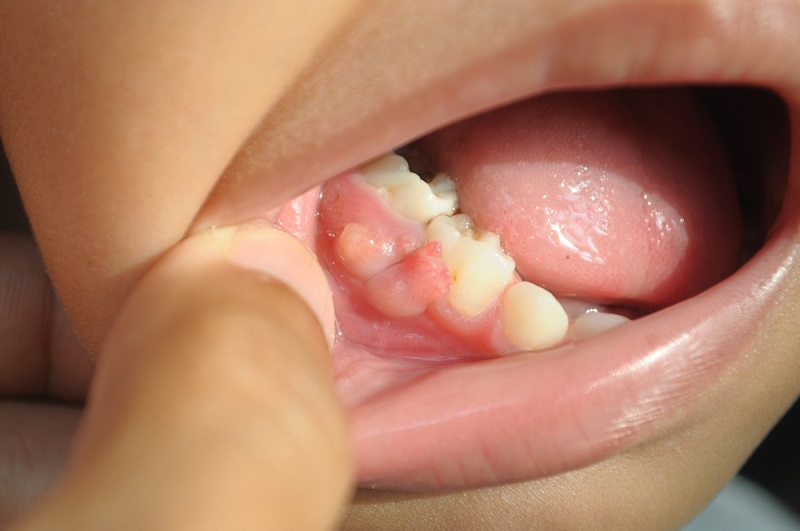

In the management of compromised dentition, the recurrence of pathology presents a pivotal decision point. The presentation of a bump on gum after root canal—indicative of chronic apical abscess—moves the tooth from a "stable" category to a "failing" category. As a senior consultant at Luxe Smile Studio, my role is to evaluate the strategic viability of retaining such a tooth. We must weigh the prognosis of retreatment against the predictability of extraction and implant replacement. This is not merely about treating an infection; it is about forecasting the 5- and 10-year survival capability of the dental unit in the context of the patient's overall health and financial investment.

The bump on gum after root canal is essentially a drain for a bony cavity. We must evaluate the size of this lesion via CBCT (3D imaging). If the lesion has eroded the buccal cortical plate significantly, or encroaches on the sinus or nerve canal, the risk of retaining the tooth increases. Prolonged retention of a failing tooth consumes the very bone needed for a future implant. Strategically, it is sometimes wiser to extract a tooth with a bump on gum after root canal sooner rather than later to preserve the alveolar ridge for replacement therapy.